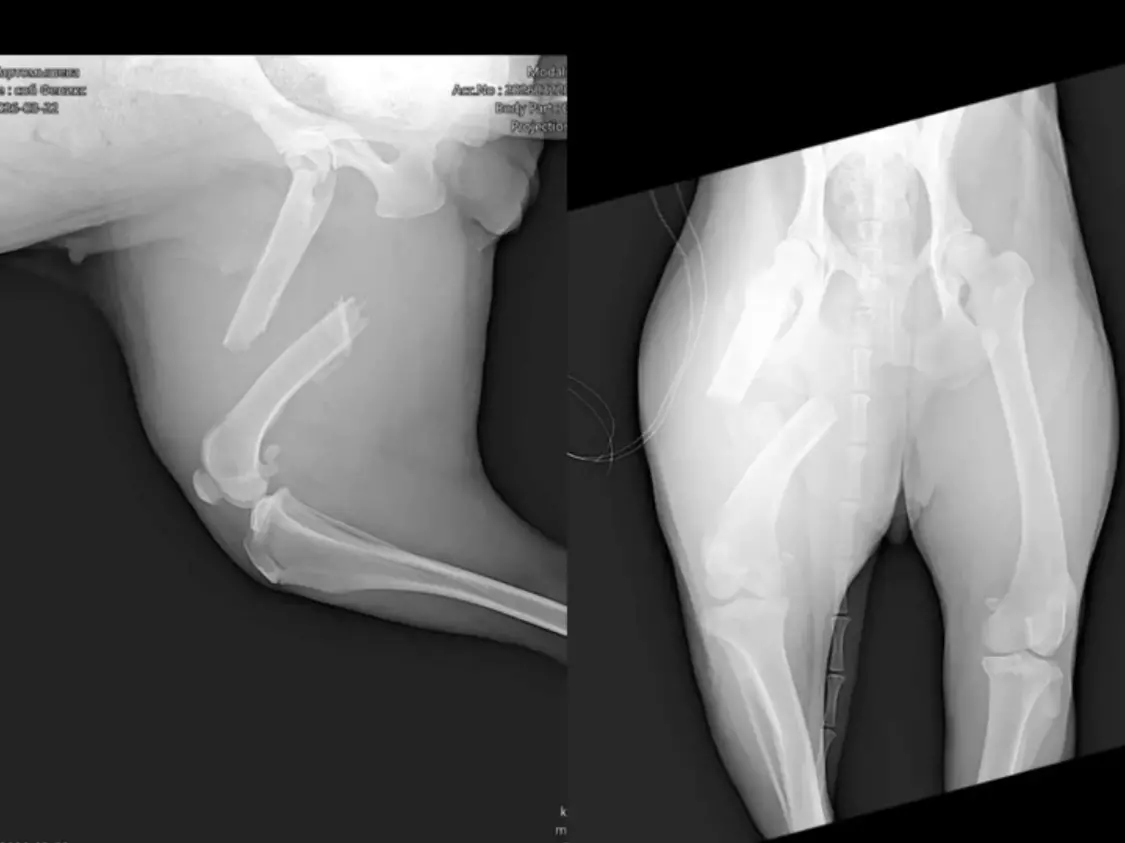

Травмированное животное отвезли в клинику Ростова. Врачи шокировали волонтеров — уже долгое время Сэнди ходила со сложным переломом берцовой кости с большим смещением.

Днем 25 марта псу провели операцию, которая длилась целых пять часов.

Сэнди уже даже стала опираться на эту лапу фактически без опоры на кость. Был риск, что лапу придётся удалить, но врач с огромным трудом освободил кости для наложения металлоконструкции.

Врачи смогли буквально по кусочкам «собрать перелом» на реконструктивную пластину. Врачи и волонтеры надеются на восстановление кровообращения в тканях.